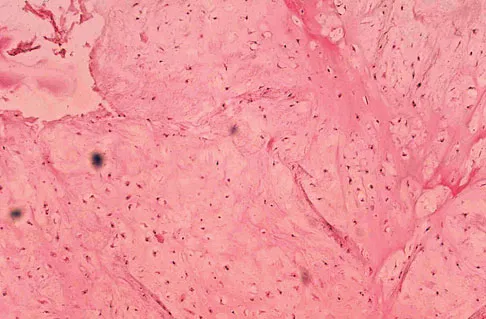

A 7-year-old girl has had a painful forearm for the past 2 months. Examination reveals fullness on the volar aspect of the forearm. Radiographs and an MRI scan are shown in Figures 42a through 42c. Biopsy specimens are shown in Figures 42d and 42e. What is the most likely diagnosis?

Explanation